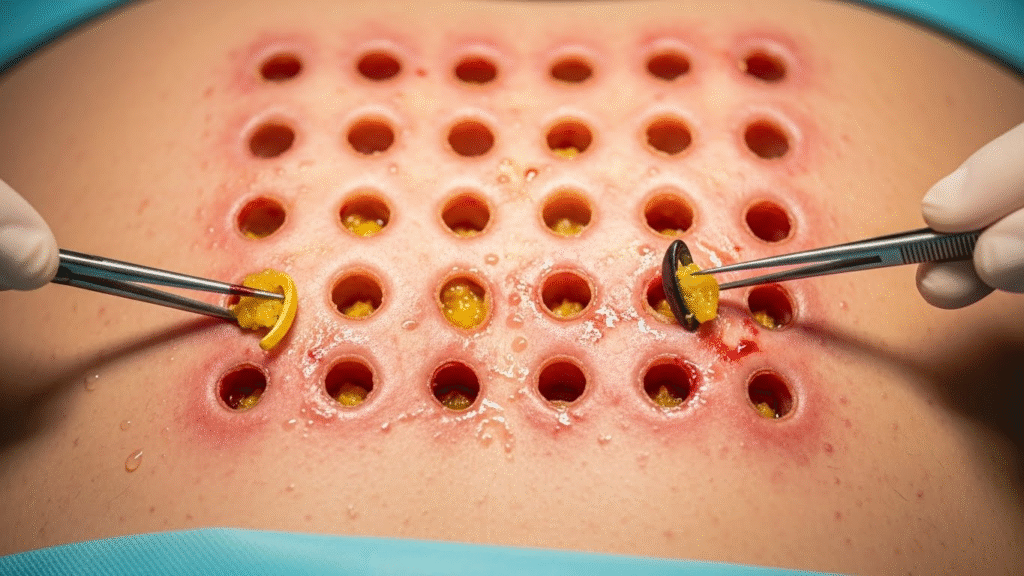

But the moment the first incision was made, doctors froze.

A thick, deep pocket opened up —

and inside were multiple cyst sacs, stacked and packed like tiny bags of trapped oil.

Each sac was filled with:

- Hardened yellowish wax

- Old, compacted oil

- Thick white paste

- Years of dead skin buildup

⚠️ The Removal Process: Not for the Weak-Hearted

One squeeze after another, the doctor removed:

- Small pea-sized cysts

- Long string-like sacs

- Thick rubbery plugs

- A giant lump at the deepest layer

Each removal looked like pulling out tiny balloons filled with years of trapped material.